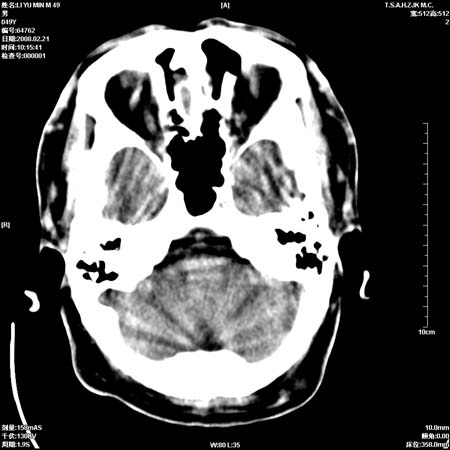

男性, 49岁, 头痛, 行ct检查后, 我科一名大夫报了蛛网膜下腔出血, 请大家讨论!

大脑纵裂池及鞍上池应该有蛛血

可能性脑动脉硬化所致